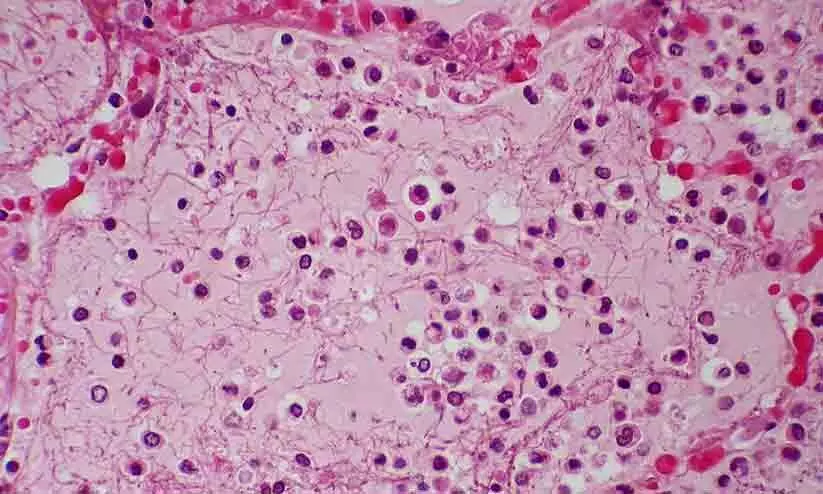

ചൈനയിൽ കുട്ടികളിലാണ് ശ്വാസകോശ സംബന്ധമായ രോഗം വ്യാപകമാകുന്നത്.അസുഖങ്ങൾ വർധിക്കുന്നതിനെക്കുറിച്ചും ന്യൂമോണിയ റിപ്പോർട്ട് ചെയ്യപ്പെട്ട ക്ലസ്റ്ററുകളെക്കുറിച്ചുമുള്ള വിശദാശംങ്ങൾ ചൈനയോട് ലോകാരോഗ്യ സംഘടന (ഡബ്ല്യൂ.എച്ച്.ഒ) ആവശ്യപ്പെട്ടിരുന്നു. വടക്കൻ ചൈനയിലാണ് രോഗം ആദ്യമായി റിപ്പോർട്ട് ചെയ്തത്. കുട്ടികളിൽ പടർന്ന് പിടിച്ചതിനാൽ രോഗവ്യാപനം കൂടുതലുള്ള പ്രദേശങ്ങളിൽ വിദ്യാഭ്യാസ സ്ഥാപനങ്ങൾ അടച്ചിട്ടിരിക്കുകയാണ്. പനി, ചുമ, ശ്വസിക്കാൻ ബുദ്ധിമുട്ട് എന്നിവയാണ് പ്രാഥമികമായി റിപ്പോർട്ട് ചെയ്യപ്പെട്ട ലക്ഷണങ്ങൾ. ഇത് സാധാരണ ന്യുമോണിയയുമായി സാമ്യമുള്ളതാണെങ്കിലും തീവ്രത പതിന്മടങ്ങാണ്.